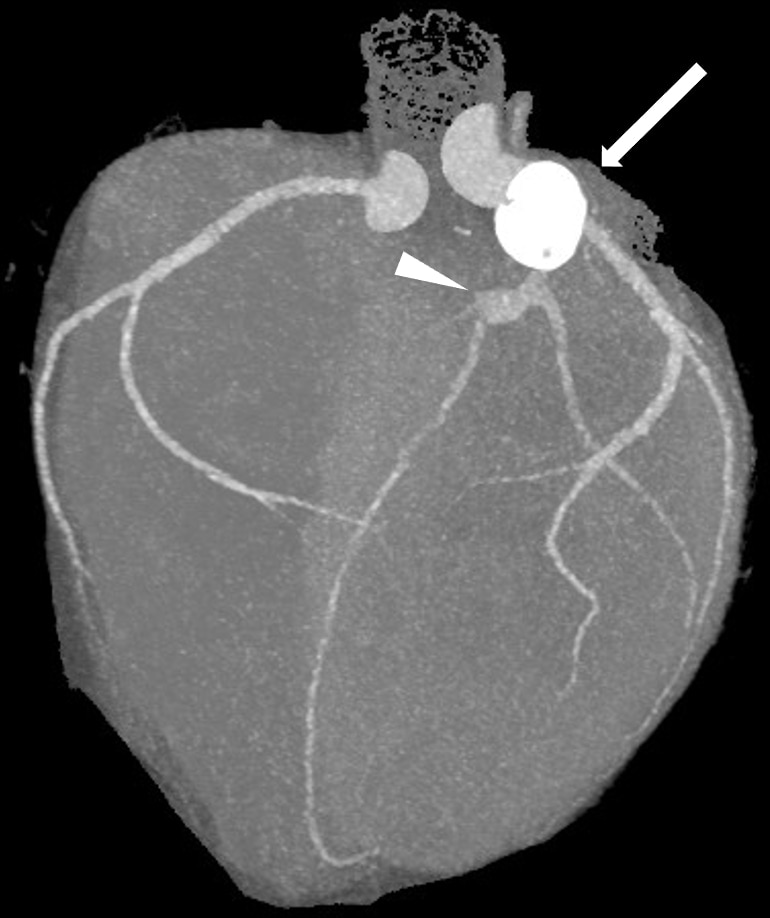

図1.VR

#6に石灰化を伴った16㎜大の巨大動脈瘤(➡)、#7に石灰化を伴わない動脈瘤(➤)を認める。